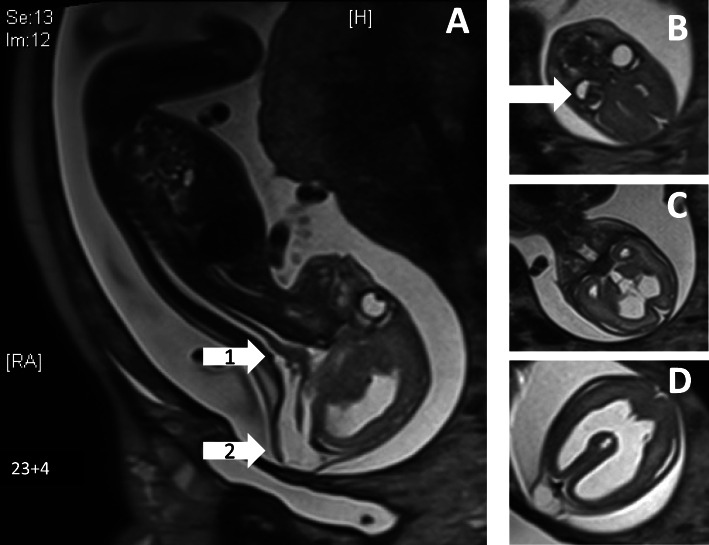

Fig. 3.

Prenatal MRI scan at 23 + 4 weeks of gestation; a hypoplastic cerebellum (white arrow 1), occipital meningocele (white arrow 2); b persistent hypoplastic primary vitreous body (white arrow); c + d internal hydrocephalus